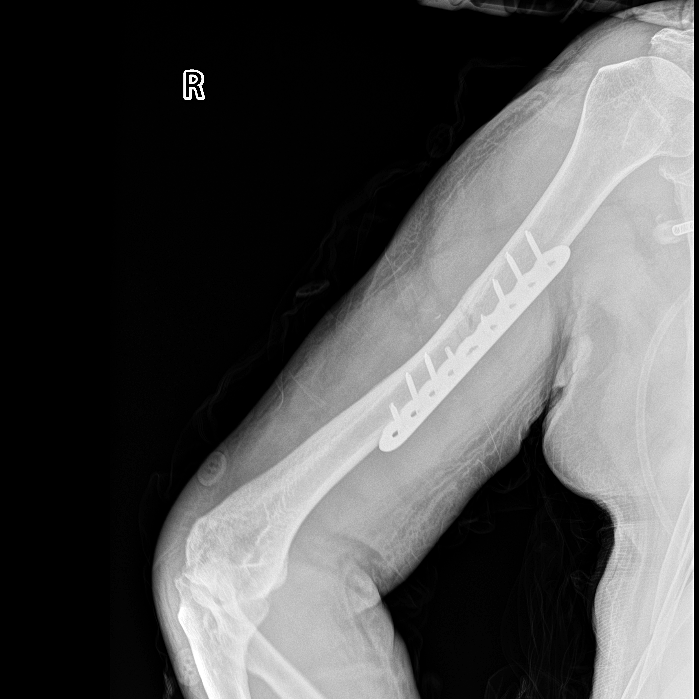

【右肱骨骨折术后】

胸外科医生率先出手,紧急置入胸腔闭式引流管,成功排出压迫肺部的血气胸,为呼吸功能争取喘息空间;神经外科团队紧盯颅内情况,精准用药控制脑挫裂伤引发的脑水肿,严防脑出血恶化;骨科团队则针对右侧肱骨骨折制定手术方案,为后续康复打下基础。

入院第37天,经过多学科团队的通力协作,阿公的颅内血肿基本吸收,骨折部位顺利愈合,呼吸功能恢复正常,各项生命体征平稳,终于达到转出ICU的标准。